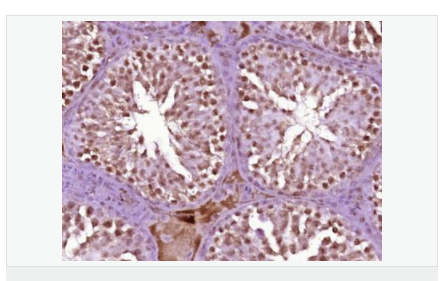

| 產(chǎn)品應用 | ELISA=1:5000-10000 IHC-P=1:100-500 IHC-F=1:100-500 ICC=1:100-500 IF=1:100-500 (石蠟切片需做抗原修復) not yet tested in other applications. optimal dilutions/concentrations should be determined by the end user. |

| 產(chǎn)品介紹 | This gene encodes a protein which contains a hinge region domain found in members of the SMC (structural maintenance of chromosomes) protein family. [provided by RefSeq, Dec 2011] Function: Required for maintenance of X inactivation in females and hypermethylation of CpG islands associated with inactive X. Involved in a pathway that mediates the methylation of a subset of CpG islands slowly and requires the de novo methyltransferase DNMT3B (By similarity). Required for DUX4 silencing in somatic cells. Subcellular Location: Chromosome DISEASE: The disease is caused by mutations affecting the gene represented in this entry. SMCHD1 mutations lead to DUX4 expression in somatic tissues, including muscle cells, when an haplotype on chromosome 4 is permissive for DUX4 expression. Ectopic expression of DUX4 in skeletal muscle activates the expression of stem cell and germline genes, and, when overexpressed in somatic cells, DUX4 can ultimately lead to cell death. Disease description:A degenerative muscle disease characterized by slowly progressive weakness of the muscles of the face, upper-arm, and shoulder girdle. The onset of symptoms usually occurs in the first or second decade of life. Affected individuals usually present with impairment of upper extremity elevation. This tends to be followed by facial weakness, primarily involving the orbicularis oris and orbicularis oculi muscles. SWISS: A6NHR9 Gene ID: 23347 Database links: Entrez Gene: 23347 Human Entrez Gene: 74355 Mouse Omim: 614982 Human SwissProt: A6NHR9 Human SwissProt: Q6P5D8 Mouse Unigene: 8118 Human Unigene: 194450 Mouse Important Note: This product as supplied is intended for research use only, not for use in human, therapeutic or diagnostic applications. |